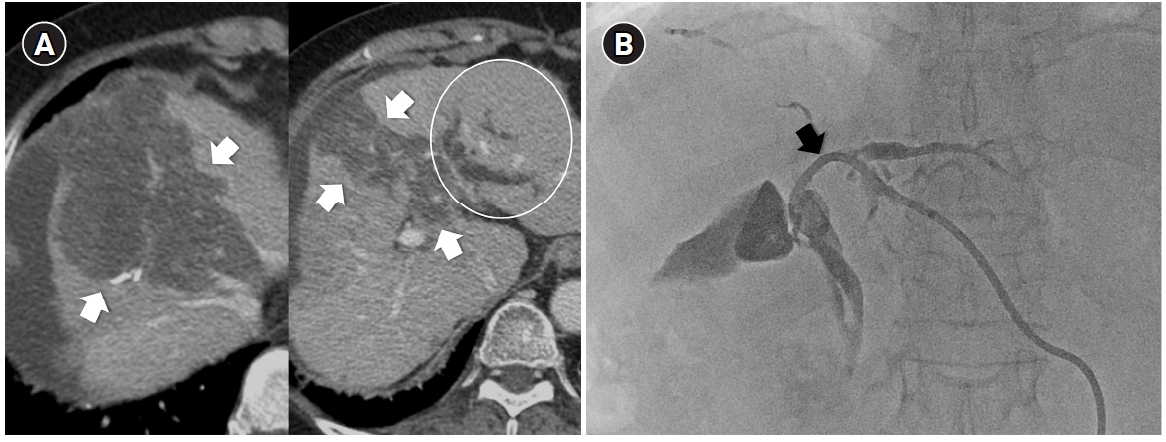

Radiation subsegmentectomy in an 86-year-old man with a single nodular hepatocellular carcinoma. (A) Liver magnetic resonance imaging shows a 2.2-cm hypervascular tumor (arrow) with exophytic growth in segment 6. (B) Hepatic arteriography shows a hypervascular tumor (arrows), and the microcatheter was advanced into a subsegmental branch of A6 (right side image). A total activity of 0.35 GBq of glass microspheres was infused. (C) Post-treatment Y-90 positron emission tomography shows intense uptake at the tumor (arrow), confirming a perfused liver dose of 508.7 Gy and a tumor dose of 1,794.7 Gy. Voxel-based dosimetry showed a D95 of 625 Gy and a V200 of 100% (D95: the minimum dose delivered to 95% of the target volume, V200: the percentage of target volume receiving ≥200 Gy). (D) Twenty-month follow-up computed tomography shows complete response with dystrophic calcification (arrow).

Fig. 1. Radiation subsegmentectomy in an 86-year-old man with a single nodular hepatocellular carcinoma. (A) Liver magnetic resonance imaging shows a 2.2-cm hypervascular tumor (arrow) with exophytic growth in segment 6. (B) Hepatic arteriography shows a hypervascular tumor (arrows), and the microcatheter was advanced into a subsegmental branch of A6 (right side image). A total activity of 0.35 GBq of glass microspheres was infused. (C) Post-treatment Y-90 positron emission tomography shows intense uptake at the tumor (arrow), confirming a perfused liver dose of 508.7 Gy and a tumor dose of 1,794.7 Gy. Voxel-based dosimetry showed a D95 of 625 Gy and a V200 of 100% (D95: the minimum dose delivered to 95% of the target volume, V200: the percentage of target volume receiving ≥200 Gy). (D) Twenty-month follow-up computed tomography shows complete response with dystrophic calcification (arrow).